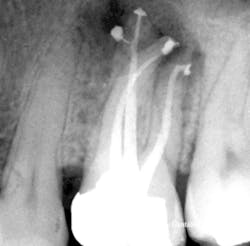

In 1989, I conceived of a way to radically simplify 3-D obturation.This new method collapsed Schilder's Vertical Condensation Technique of three-to-five heating and packing steps requiring five minutes per canal, into a downpack that required just two procedural steps and less than 15 seconds per canal to complete. While it was my intention was to simplify Schilder's procedure, the surprise result was a "centered" condensation technique that, despite the huge reduction in time and skills needed, actually provided superior obturation results that moved more gutta-percha into lateral complexities than vertical condensation (figures 2, 3, 4a, and 4b). (2)

Figure 3: Illustration of "centered" condensation, with its streaming effect. The best analogy for the CW Technique is that it is the inverse of analog impressioning. The impression tray becomes the electric heat plugger, the heavy-bodied impression material is like thermo-plasticized gutta-percha, and the thin-bodied material is analogous to sealer.